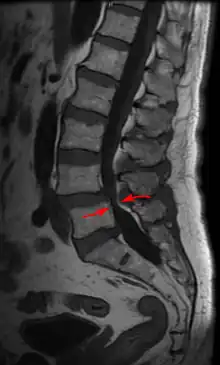

| Lumbar vertebra showing central stenosis and lateral recess stenosis. | |